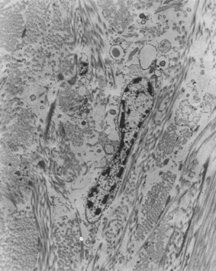

The developmental process of the human sclera progresses from anterior to posterior and from inside to outside.4 The human eye develops early in week 4 as an evagination from the ventral lateral aspect of the neural tube or neuroectoderm at the level of the forebrain in the diencephalon. The end of the evagination becomes slightly dilated to form the optic vesicle. At the same time a small area of surface ectoderm overlying each optic vesicle thickens, forming the lens placode, which invaginates to become the lens vesicle. At this time there are three waves of neural crest mesenchymal invasion. The first is responsible for the corneal endothelium and trabecular meshwork, the second for the corneal and scleral fibrocytes, and the third for iris and choroidal stroma. By week 5 of development each optic vesicle invaginates to form the double-layered optic cup or neuroectoderm that is surrounded by neural crest which is also of ectodermal origin. The differentiation of neural crest cells into sclera and choroid occurs by week 6 of development in humans in the region anterior to the equator (about day 43 of development),5 progresses backward to the equator by week 8, and reaches the posterior pole by week 12.1 This differentiation is induced by the retinal pigment epithelium.6–8 The sclera as well as the choroid and the retinal pigment epithelium requires the presence of the developing lens for normal growth and change in shape, structure, and function.1 By the 4th month circularly oriented scleral fibers form the scleral spur, and by the 5th month scleral fibers around the axons of the optic nerve form the lamina cribrosa.1,4 Arrest of fetal development at this stage or the failure to lay down new collagen on the inner aspect of the posterior sclera might well account for some of the staphylomatous changes found in congenital myopia and disc changes found in some patients with congenital glaucoma. Ultrastructural studies show that developmental events of the sclera begin in the region anterior to the equator at approximately day 43.4,5 The late mesenchymal cells or very early fibroblasts of the anterior portion possess elongated nuclei and many glycogen granules and lipid vacuoles whereas those of the posterior portion possess round-to-oval nuclei and few glycogen granules and lipid vacuoles. The late mesenchymal cells or very early fibroblasts of the anterior and posterior portions contain many free ribosomes and polyribosomes, as well as immature rough-surfaced endoplasmic reticulum and Golgi complex. The early fibroblasts begin the synthesis of glycoproteins, glycosaminoglycans (especially hyaluronic acid), collagen, and elastin between day 43 and 50, thus filling the intercellular space. Developmental events directed from inside outward begin at week 7.2 with a marked increase in the inner portion in glycogen granules and lipid droplets of the cells, and in number and average diameter of collagen fibrils. Cytodevelopment of the sclera is characterized by decrease of ribosomes, polyribosomes, glycogen granules, and lipid vacuoles, and by increase of rough-surfaced endoplasmic reticulum and Golgi complex components. Development of intercellular substances is characterized by an increase in the number and average diameter of collagen fibrils (Fig. 1) and in the amount of elastic deposits with electron-translucent central cores. By week 10.9 there are no more differences between the inner and outer portions. By week 13 there are no more differences between the anterior and posterior portions. By week 24, fetal sclera has the same ultrastructural characteristics as adult sclera. Between week 6 and week 24 there is a threefold increase in thickness, possibly by progressive laying down of collagen fibrils on its inner aspect as more mature collagen fibrils are found in the outer part of the sclera and the younger smaller collagen fibrils on its inner aspect; thereafter the rate of increase diminishes rapidly. Defects in synthesis of extracellular matrix components during scleral development may account for conditions such as Marfan syndrome, osteogenesis imperfecta, pseudoxanthoma elasticum, Ehlers-Danlos syndrome, congenital myopia, and nanophthalmos. Immunohistochemical studies show that the extracellular matrix of fetal sclera has the collagens I, III, IV, V, and VI, the glycosaminoglycans dermatan sulfate, heparan sulfate, hyaluronic acid, and chondroitin sulfate, and the glycoproteins fibronectin, vitronectin, and laminin.9 Collagens II and VII are not present. Collagens play a major role in strength (collagen I), resiliency (collagen III) and structural integrity (collagens IV, V, VI); glycosaminoglycans in distensibility; and glycoproteins in cell adhesion, growth, differentiation and migration, as well as in other extracellular matrix component organization. Collagen VIII may also be present in human fetal sclera.10 Development of scleral extracellular matrix from fetus into the adult includes increase of collagens I, III, and VI, and decrease of collagen IV and VIII, hyaluronic acid (Fig. 2), fibronectin, vitronectin, and laminin.9,10 By the time the tissue is mature, collagen IV, although abundant in fetal tissue, has almost completely disappeared, except in blood vessels. Heparan sulfate is identified in fetal and adult sclera in small amounts. Increase of collagens I, III, and VI may account for the increase in strength, resiliency, and structural integrity of adult sclera. Decrease of hyaluronic acid may explain the decrease of distensibility of adult sclera. Decrease of fibronectin, vitronectin, and laminin may suggest they play a major role in directing developmental events during the younger gestational periods, including cell and extracellular matrix organization. POSTNATAL DEVELOPMENT AND AGE-RELATED CHARACTERISTICS Scleral development is determined by the genetic signaling to the fibrocytes of the sclera, and by the concomitant development of the adjacent structures such as lens, retina, choroid, and the production of aqueous by the ciliary body. During this period of growth there is an increase in axial length in order to acquire a state of emmetropia. This increase in axial length occurs in two stages, an infantile phase which is up to 3 years and then a slower juvenile phase which is up to 13 years; after this age the eye is fully developed. The postnatal sclera is relatively thin, allowing the pigment cells of the choroid to show through, giving a bluish color. It is also somewhat distensible, allowing the sclera to stretch as a result of increased intraocular pressure in infantile glaucoma (buphthalmic globe). The relatively thin, bluish, distensible, small, and translucent postnatal sclera gradually becomes thicker, whiter, less distensible, larger, and more opaque as the eye goes through childhood and puberty. Although the adult sclera is poorly distensible, ectasias (localized protrusions of thin sclera) or staphylomas (localized protrusions of thin sclera lined by uveal tissue) can appear at any age after damage (trauma or inflammation). The water content of the adult sclera ranges from 65% to 75%.11 The sclera appears opaque if the water content is between 40% and 80% but becomes translucent if it falls below 40% or rises above 80%.12 This is especially evident in surgical procedures such as strabismus surgery or retinal detachment in which conjunctiva and extraocular muscles are temporally removed from the underlying sclera. The exposed sclera becomes dry and therefore appears translucent unless it is continuously moistened. Similar changes occur after removal of perilimbal conjunctiva in surgical procedures such as excision of pterygium or other limbal lesions. The exposed sclera, adjacent to small elevations of conjunctiva, becomes dry because of the interference in the lubricating effect of the tear film. The dry spots, called dellen, dissappear after rehydration of the area with artificial tears or eye patching. The increase in transparency after inflammation is the result of rearrangement of the fibrils of the sclera and physiochemical changes; it is only rarely caused by true thinning of the sclera. In the elderly, the sclera is even less distensible, has decreased water content, and contains fewer glycosaminoglycans.13 This is the result of a progressive cross-linking of the lysine residues of collagen and a decrease in the size of the interfibrillar spaces, possibly as the result of changes within the proteoglycans. Other age-related changes are the subconjunctival deposition of lipids such as cholesterol esters, free fatty acids, triglycerides, and sphingomyelin, which give the sclera a yellowish color.14,15 Calcium phosphate may also be deposited in small rectangular or ellipsoid areas with a vertical axis longer than the horizontal one (approximately 6 mm high and 1 mm wide) just anterior to the insertions of medial or lateral rectus muscles. These slate-gray areas are called senile scleral plaques and usually occur in individuals over 70 years of age.16,17 The cause is uncertain but some etiologic possibilities taken either individually or in combination include ischemia secondary to atherosclerosis of the anterior ciliary arteries,18 dehydration,19 constant stress by the rectus muscles,20 and actinic damage from solar irradiation.17 The collagen fibrils themselves become thicker and less uniform, especially in the region of the muscle insertions. Here the sclera becomes progressively thinned, increasing the color contrasts between one part of the sclera and the next. |